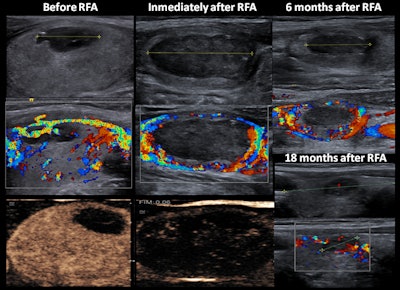

In theory, moving shots create a cylindrical effect in the RF ablation, but, in real cases, backward movement is based on step-by-step intervals that create a beaded cone-shaped cylinder, they explained. CEUS is performed before removing the needle from the nodule, and this defines triangular zones at the periphery without ablation and allows completion of the treatment. It is essential to prevent the needle or the electrode from moving when the patient swallows or talks.

"Elastography performed in several of our patients after RF ablation shows that there was an important component of fibrosis during the follow-up," the authors pointed out.